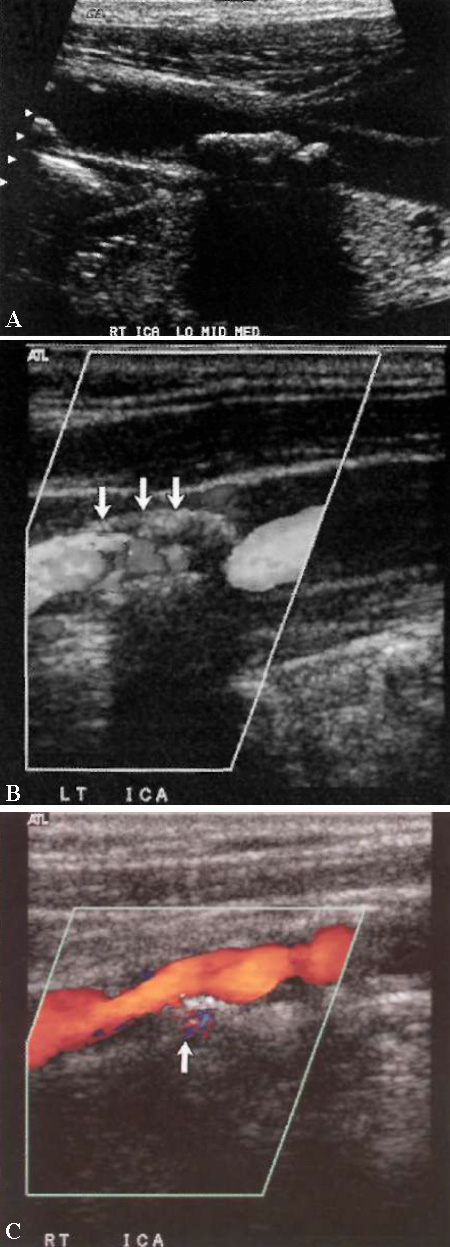

Язва бляшки представляет собой дефект или полость, размеры которой более 2×2 мм. Изъязвленная бляшка на ангиографии представляет собой важный прогностический признак высокого риска цереброваскулярных осложнений. Ангиография и УЗИ обладают низкой чувствительностью и низкой специфичностью при диагностике изъязвленных бляшек. Цветовая допплерография позволяет обнаружить область обратного кровотока в пределах изъязвленной бляшки (фото 9).

УЗИ: Атеросклеротическая бляшка в сонной артерии

Фото 9. Атеросклеротическая бляшка в сонной артерии. А – кальцинированная бляшка с акустическим затенением. В – стрелкой обозначена некальцинированная (мягкая) бляшка. С – изъязвленная бляшка: стрелкой обозначен поток внутри бляшки